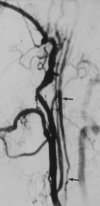

Background and purpose: Two large trials indicated that endarterectomy was less beneficial for symptomatic patients with internal carotid artery (ICA) near occlusion than for patients who had severe stenosis without near occlusion. Near occlusions complicate ratio calculations of ICA stenosis and require attention to detail for identification. The goal is to provide diagnostic criteria, illustrate identifying features, estimate accuracy of identification, and assess prognosis for patients with near occlusion.

Methods: We re-reviewed 1216 patients with severe (> or =70%) stenosis on angiography in the North American Symptomatic Carotid Endarterectomy Trial and European Carotid Surgery Trial. One of 5 (n = 262) had 2 or more criteria for near occlusion: (1) delayed cranial arrival of ICA contrast compared with external carotid artery (ECA); (2) intracranial collaterals seen as cross-filling of contralateral vessels or ipsilateral contrast dilution; (3) obvious diameter reduction of ICA compared with opposite ICA; or (4) ICA diameter reduction compared with ipsilateral ECA.

Results: Interrater agreement, sensitivity, and specificity were excellent (0.88, 90.6%, and 93.8%, respectively). By intention to treat, 3-year risks of ipsilateral stroke for medically treated patients with near occlusion was 15.1% versus 10.9% for surgically treated (absolute risk reduction [ARR] = 4.2%; P value = .33). Patients who continued to receive treatment in the medical arm for the trial's duration had a 3-year risk of 18.3% (ARR = 7.4%; P value = .13). Medically treated patients with severe stenosis but without near occlusion had a 3-year risk of 26.0% versus surgically treated of 8.2% (ARR = 17.8%; P value < .001).